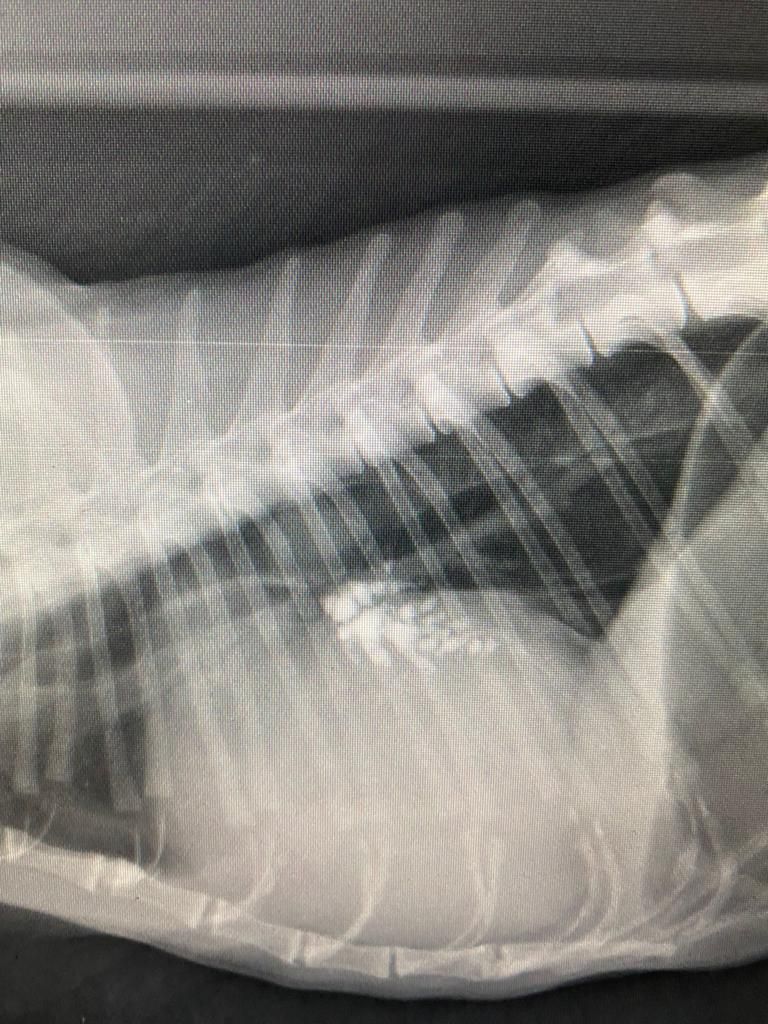

- Examen du squelette : (membres thoraciques et pelviens) ou (crâne, colonne vertébrale) : lors de boiteries, de membres douloureux,de troubles nerveux, bilans d’extension oncologique ou post-traumatique...

L’appareil radiographique émet des rayons X, tandis que le capteur les reçoit. Les rayons vont alors traverser le corps et imprimer une image de ce dernier sur le capteur.

L'image est fixe ici, nous pouvons observer correctement les structures osseuses ce qui n'est pas le cas avec l'échographie mais a contrario nous ne pouvons pas voir le mouvement des organes.